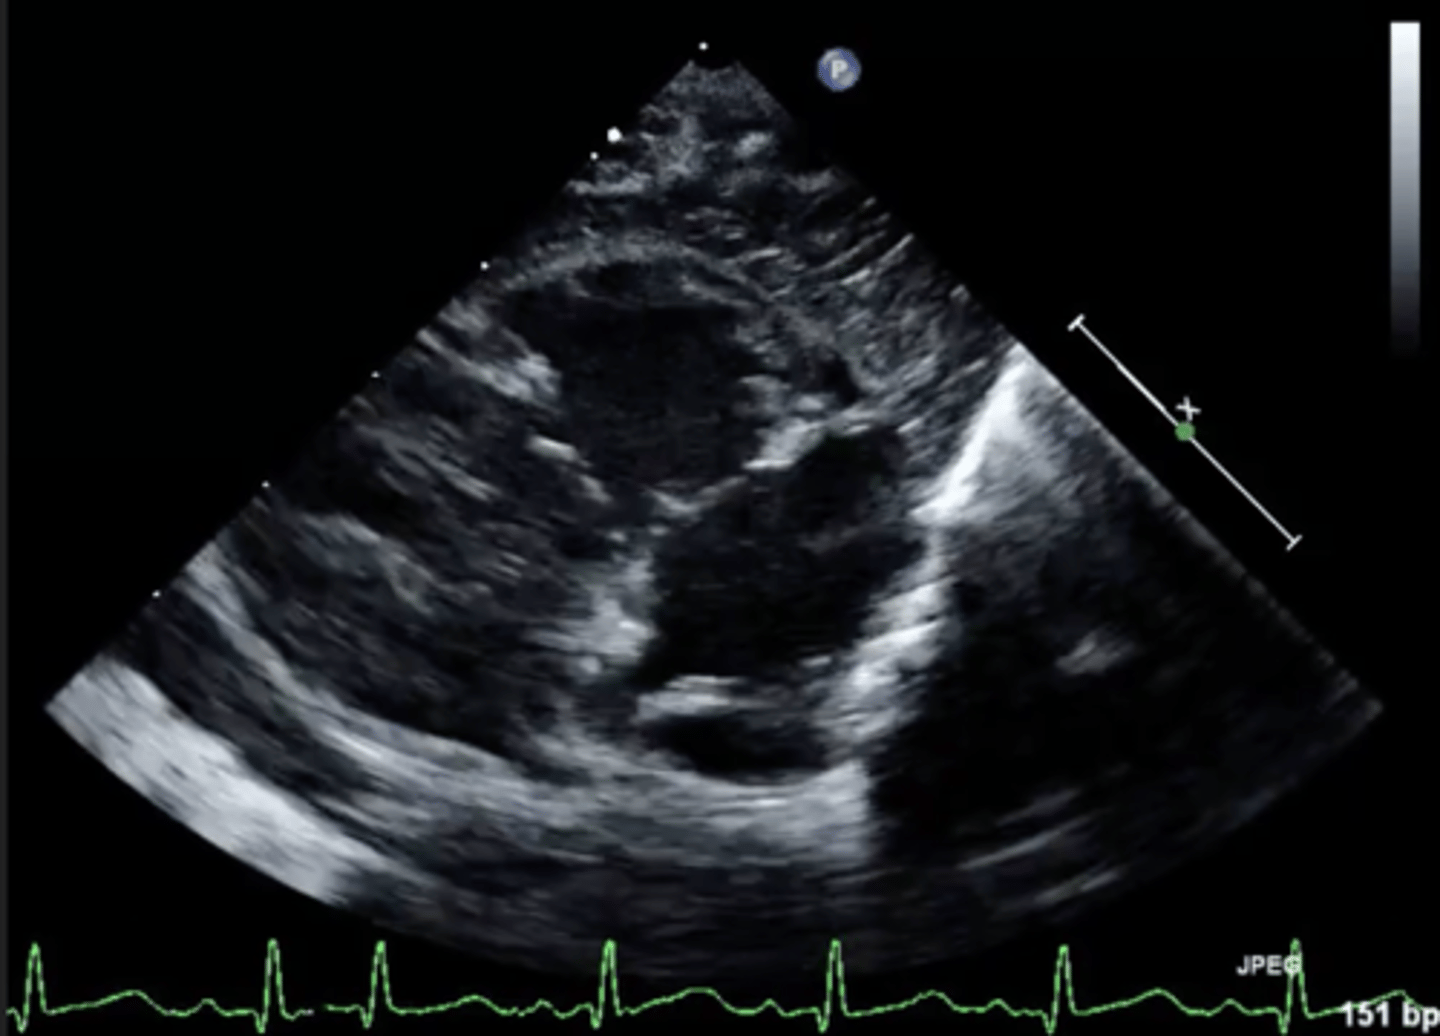

MV PLAX (top leaflet)

AMVL

MV PLAX (bottom leaflet)

PMVL